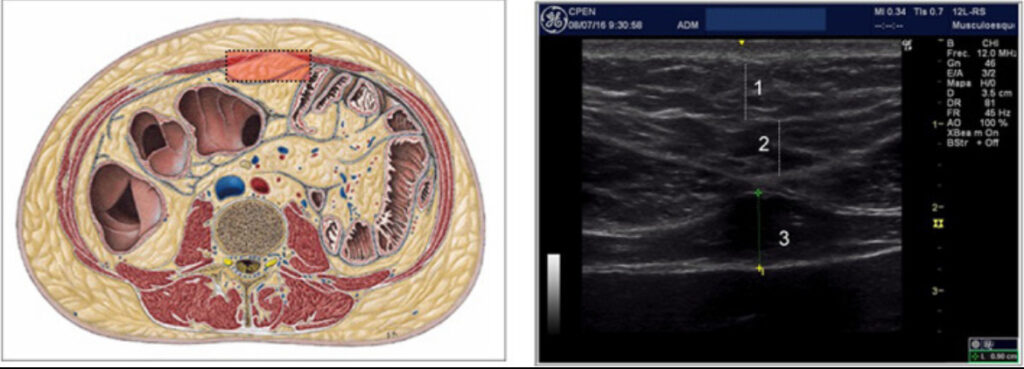

L’ecografia del tessuto adiposo, conosciuta anche come adipometria ecografica, è un esame non invasivo che utilizza ultrasuoni per osservare e misurare gli strati del corpo.

Attraverso una sonda ecografica, posso analizzare in modo preciso:

- il tessuto adiposo superficiale

- il tessuto adiposo profondo

- il tessuto muscolare

Le immagini ecografiche mostrano chiaramente i diversi strati:

- pelle

- grasso superficiale

- grasso profondo

- muscolo